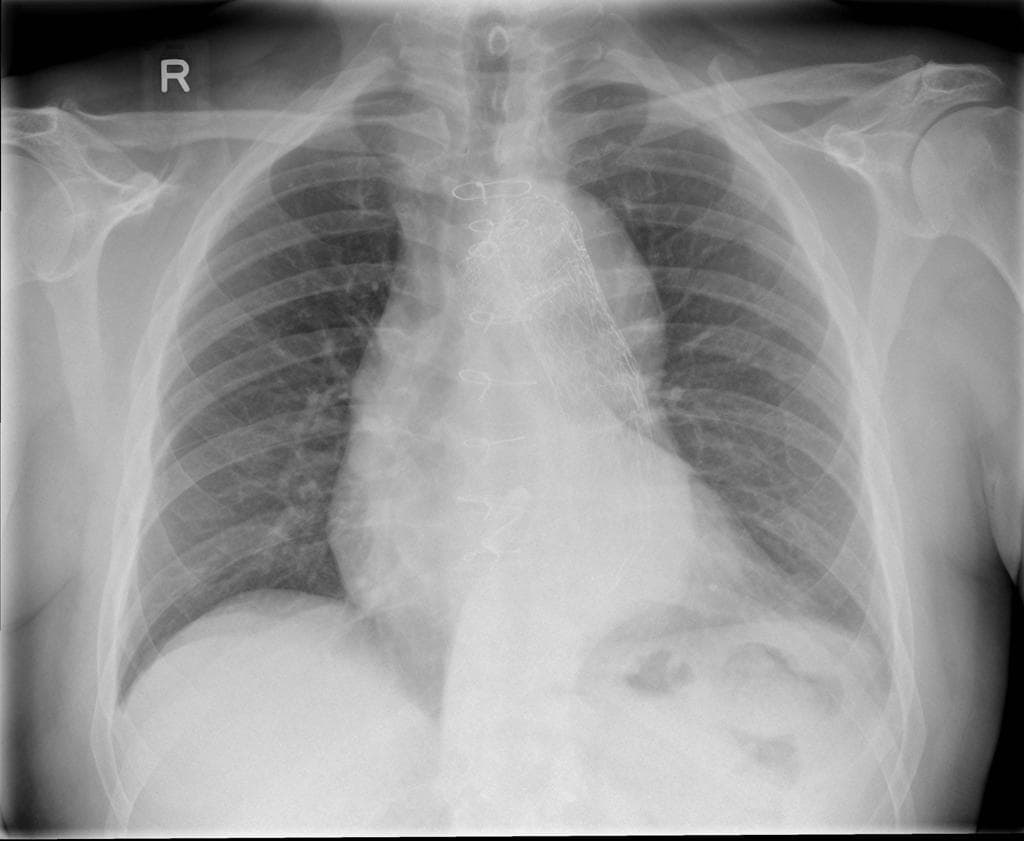

- Thấy vạt bóc tách (flap) trong động mạch chủ (aorta), xuất phát ở đoạn động mạch chủ lên (ascending aorta) ngay phía dưới gốc động mạch chủ (aortic root), xoắn dọc theo toàn bộ động mạch chủ (aorta), tạo thành buồng giả (false lumen) lớn nằm chủ yếu phía sau và chèn ép buồng thật (true lumen), buồng thật có hình bầu dục trên mặt cắt ngang.

- Toàn bộ động mạch chủ (aorta) giãn, đường kính lớn nhất tại đoạn động mạch chủ xuống ngực (descending thoracic aorta) đo được 5,1 cm.

Trường hợp này cho thấy hình ảnh bóc tách động mạch chủ (aortic dissection) loại Stanford A / DeBakey I.

Trường hợp này minh họa một ví dụ điển hình của bóc tách động mạch chủ loại Stanford A / DeBakey I, đặc trưng bởi vết rách nội mạc ở đoạn động mạch chủ lên, lan theo vạt bóc tách dọc cung động mạch chủ và động mạch chủ xuống đến động mạch chủ bụng và động mạch chậu chung. Loại bóc tách này đe dọa tính mạng do nguy cơ chèn ép tim, hở van động mạch chủ cấp, thiếu máu cơ tim và hội chứng thiếu tưới máu cơ quan. Phẫu thuật cấp cứu là cần thiết để ngăn vỡ mạch và tử vong. Các dấu hiệu hình ảnh như giãn động mạch chủ, vạt bóc tách xoắn, chèn ép buồng thật và huyết khối một phần buồng giả giúp chẩn đoán. Việc phân biệt với huyết khối thành động mạch chủ và loét xơ vữa xuyên thành là rất quan trọng vì cách xử trí khác biệt rõ rệt.